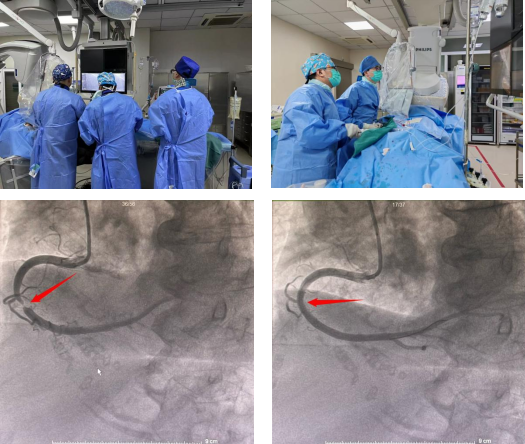

经过详细的术前准备,心内科团队拟决定为老人实施“冠状动脉造影+支架植入术”。造影显示,毛奶奶的右冠状动脉中段已次全闭塞,情况比预想更为复杂。

团队临危不乱,介入下,导丝轻柔探路,球囊扩张开路,最终一枚支架被稳稳植入最狭窄处,瞬间血流复通,生命源泉重新灌注心肌。整个过程有惊无险,成功闯过了“高龄禁区”!